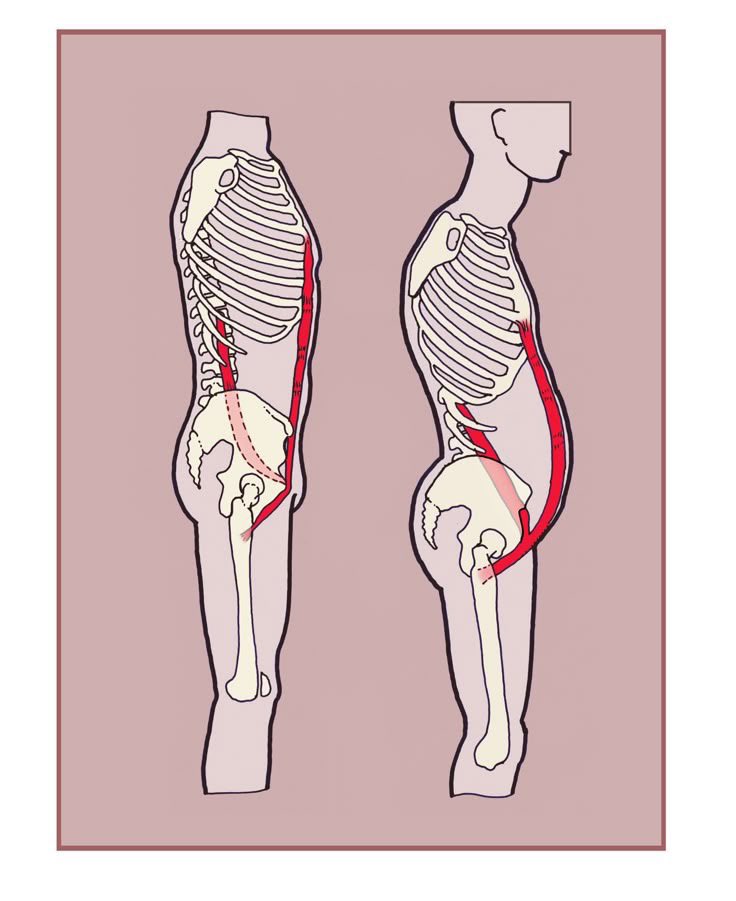

This is gonna be a very specific post, but hang on with me 99% of people are walking around with a tight and shortened front-chain and more specifically the psoas gets extremely jammed up and that messes up with your body way more than you think including tour posture and…